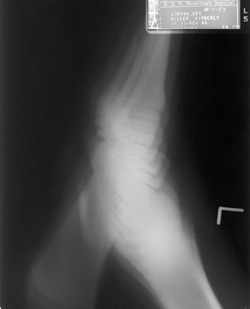

Click to enlarge Click to enlarge